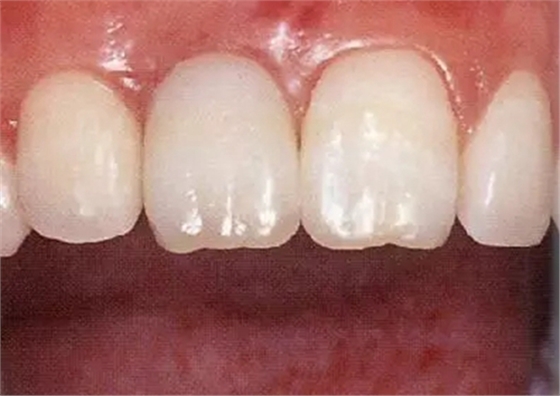

▲圖44-15,16

佩戴最終修復(fù)體時的正面口內(nèi)照和X光牙片。取得了很好的美觀狀態(tài)。

▲圖44-19,20

初診時和佩戴最終修復(fù)體時的狀態(tài)。適當修正牙冠形態(tài)后,恢復(fù)了前牙的美觀性。

▲圖44-21

6年后的狀態(tài)。